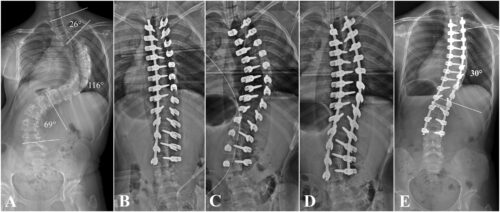

يُعد اعوجاج العمود الفقري عند المراهقين (الجنف) من أكثر مشكلات الظهر شيوعًا في فترة النمو. يظهر عادة في سن المراهقة دون سبب واضح. ومع ذلك، تشير الأبحاث الحديثة إلى أن المشكلة لا تتعلق فقط بشكل العمود الفقري، بل تمتد لتؤثر على توازن الجسم وطريقة تحكم المراهق في حركة رأسه ورقبته.

أراد الباحثون معرفة ما إذا كان المراهقون المصابون بالجنف يعانون من ضعف في الإحساس بحركة الرقبة مقارنةً بالمراهقين الأصحاء.

مجموعة مصابة بانحناء في العمود الفقري بدرجات مختلفة.

أظهرت النتائج أن المراهقين المصابين بالجنف يعانون من ضعف في الإحساس بحركة الرقبة مقارنة بالأصحاء.

لاحظ الباحثون أن بعض المشاركين لم يتمكنوا من إعادة الرأس بدقة بعد تحريكه، وكانت الانحرافات في الوضعية أكبر من المعتاد.

كما وجدوا أن ضعف الإحساس يزداد مع ارتفاع درجة الانحناء في العمود الفقري، مما يشير إلى أن الاعوجاج قد يؤثر تدريجيًا على توازن الرأس والجسم معًا.